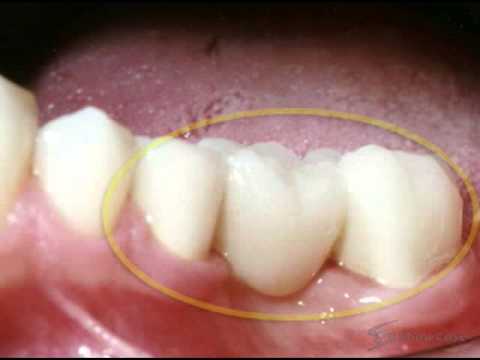

home Procedures Dental Bridges – 3 Unit Bridges Procedure Dental Bridges – 3 Unit Bridges Procedure By dentists Posted in Procedures Posted on May 8, 2017